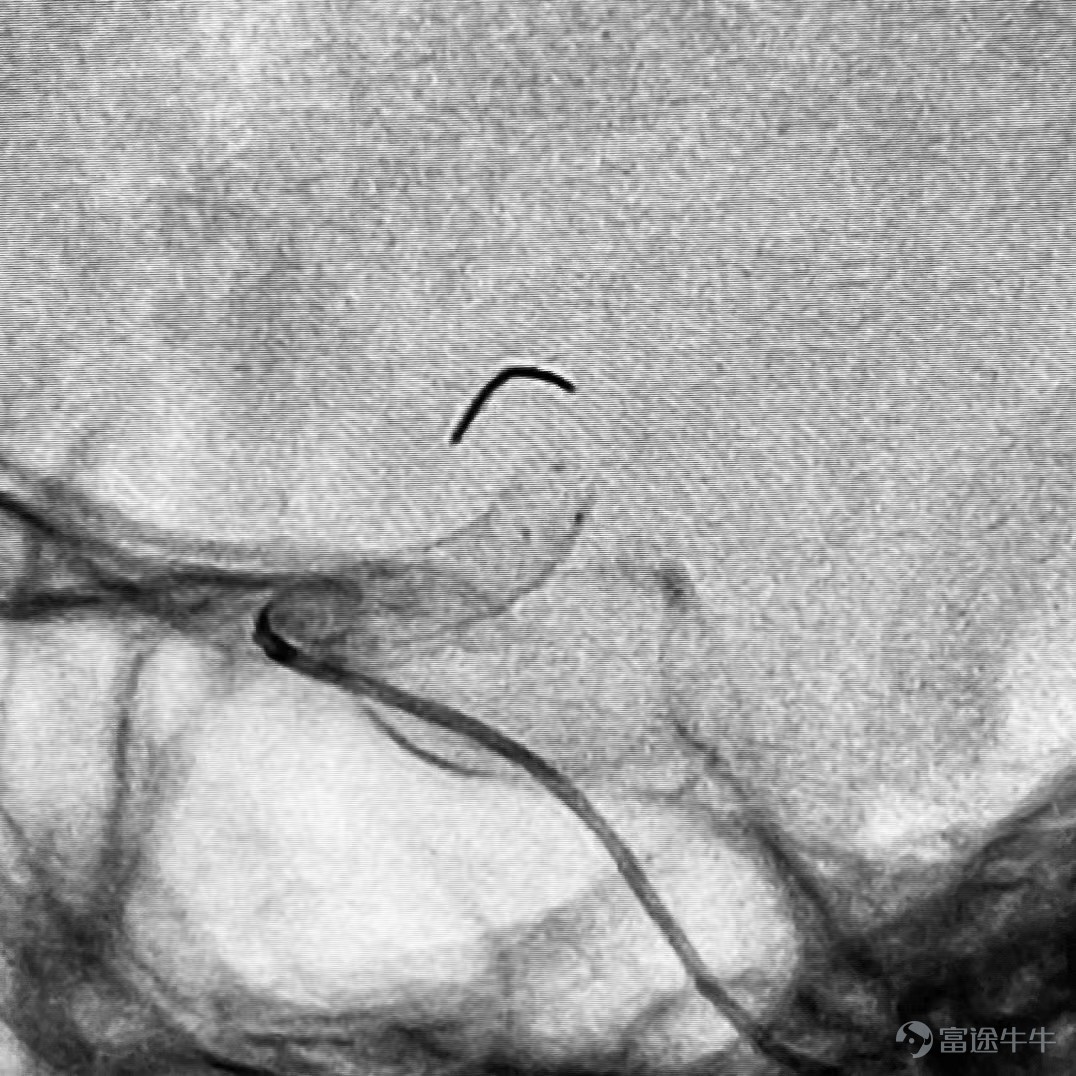

Professor Hong Bo of Changhai Hospital completed the enrollment of the first patient. The enlisted patient's internal carotid artery was curved, and the aneurysm was located in the ocular artery section. This operation was quite challenging. After surgery, Professor Hong Bo was very satisfied with the product. He said, “The 'Tongqiao Kirin' blood flow guide device performed well, the pumping process was very smooth, the adhesion determination was good after release, the contrast was obvious, the aneurysm contrast agent stayed, the tumor-carrying artery was unobstructed, and the operation went smoothly. I hope the patient has a good prognosis and a speedy recovery.”